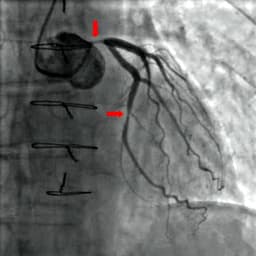

- Recent randomized controlled trial compared early intervention (PCI/CABG) to medical management for those diagnosed with moderate to severe cardiac ischemia on stress testing